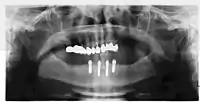

أشعة توضع استقرار الغرسات بالدعامات

طقم به اربع أماكن لتتماسك مع الغرسات

4 غرسات مستقرة في الفك السفلي - التهاب محيط بالغرسة: %9.7 [43] حتى% 40 [44]